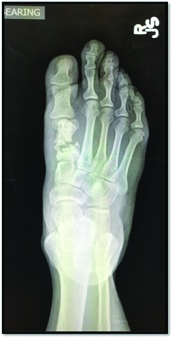

Postoperative complications of first ray surgery are inevitable due to the sheer volume of procedures performed by foot and ankle surgeons. Some of the most common first ray complications include non-unions, malunions, avascular necrosis and infection.

When patients present with these complications, precise clinical evaluations, diagnostic imaging and procedural algorithms become paramount for a timely diagnosis and implementation of effective treatments for each specific issue. Often, when we face a forefoot surgery complication, revision is warranted for optimal correction and patient outcomes.

All surgeries have a possibility of complication but certain procedures in the forefoot tend to have more risks than others. Lagaay and colleagues reported complication rates in common first ray procedures that later require further revision or fusion.1 They found complication rates of 5.56, 8.19 and 8.82 percent in 270 chevron osteotomy, Lapidus and closing base wedge osteotomy procedures respectively.